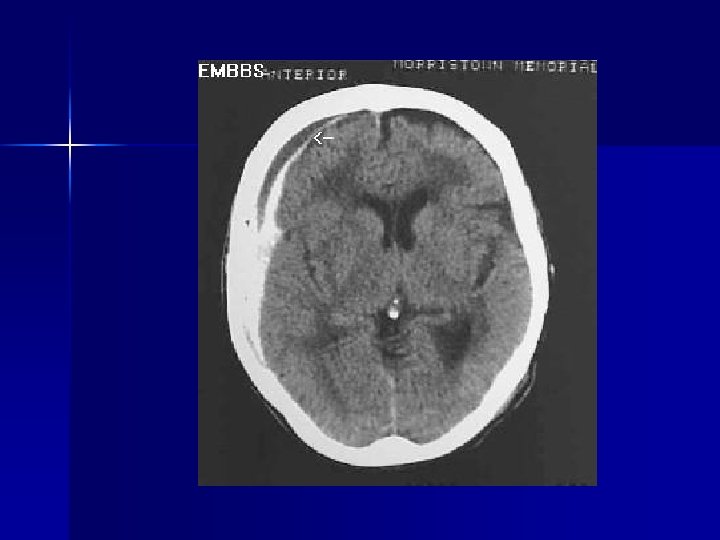

Subdural Hematoma n n Hematoma between dura mater and subarachnoid due to tearing of bridging veins Consider with history of falls, head trauma, Et. OH, elderly, anticoagulation Suspect if bruise or scalp lac, lethargy, vomiting, headache, ipsilateral dilated pupil Treatment: support ABCs, definitive treatment is neurosurgical evacuation